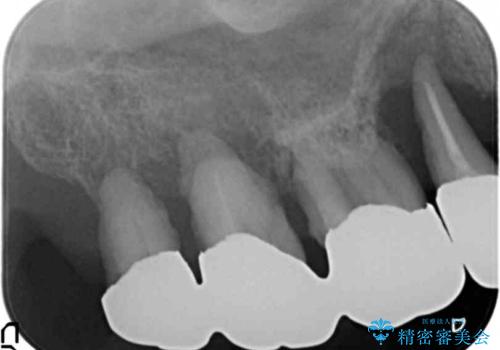

精査したところ、全顎的な重度歯周病による右上のブリッジ(右上⑧⑦⑥⑤4③)の著しい動揺を認めました。

2回目の来院時には自然脱落したとのことで右上臼歯はなくなっていました。

禁煙指導と歯周病治療後、右上臼歯部のソケットリフト及びインプラント治療(右上7654埋入)を行いました。